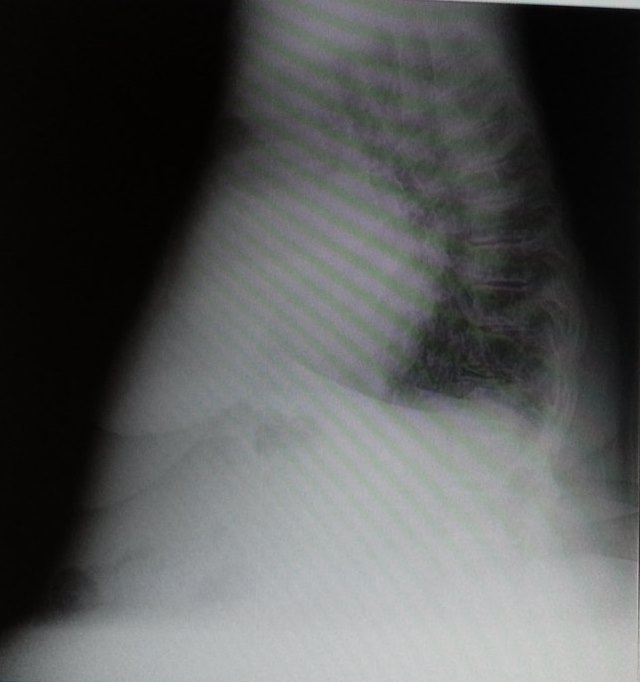

Грубо конечно, но............. (про линии Керли)и кстати правый реберно диафрагмальный синус ...................

но он все-таки проглядывает, в оригинале было видно, да и тут

Может и есть небольшое количество жидкости, но какое это имеет по большому счету значение? Тень сердца резко расширена, огромная ВПВ